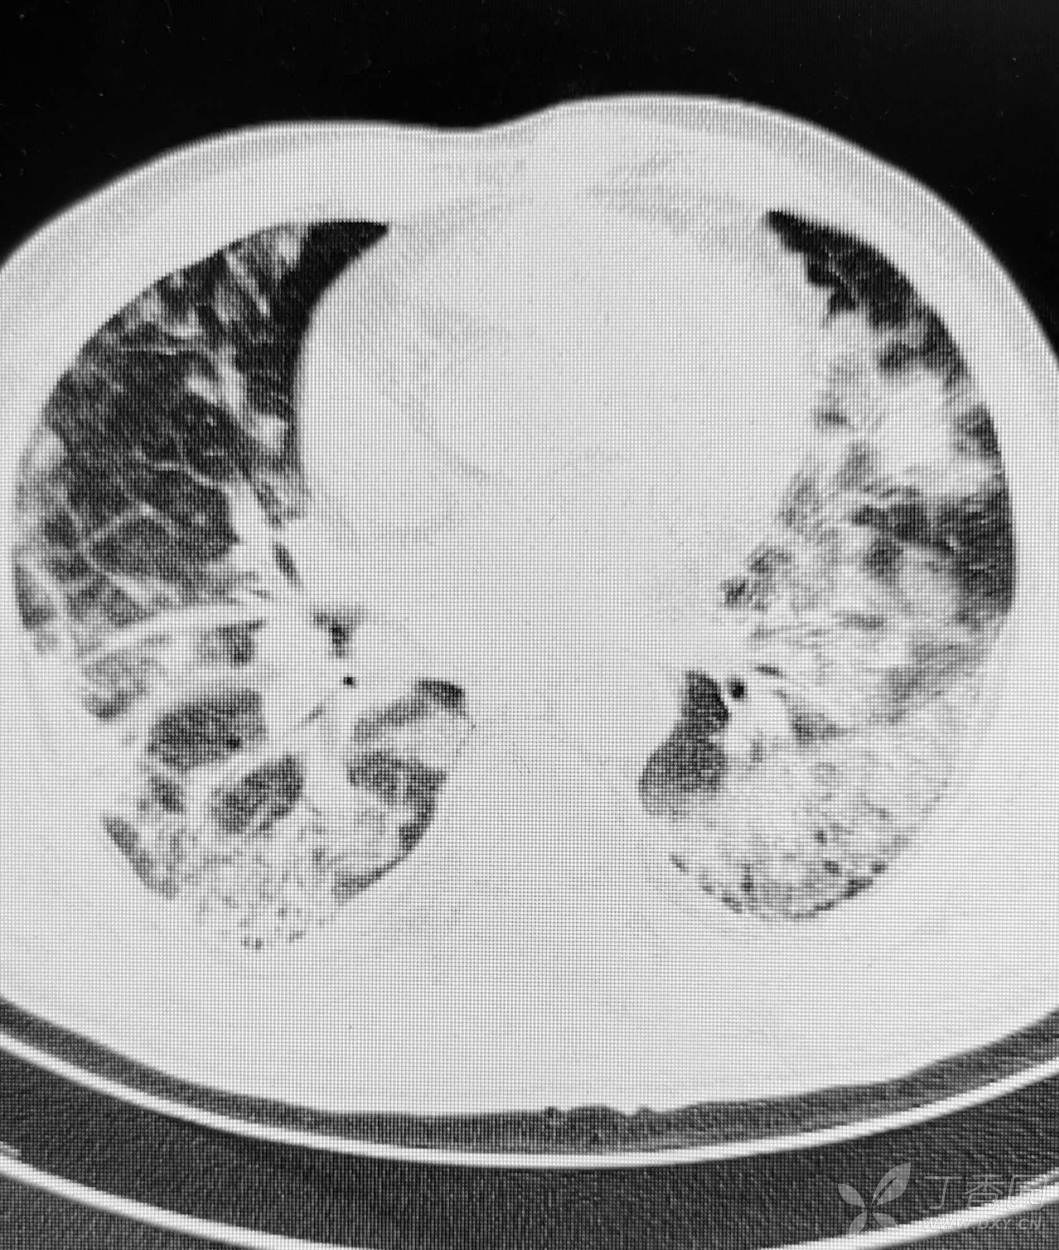

直肠癌术后两个月,接受放化疗一个月。白细胞危急值。

停化疗放疗,升白药物。白细胞增高了。

血小板仍低,血红蛋白开始降低。

胸部影像如图。

目前有血培养阳性,病原菌难以命中。痰培养阳性。